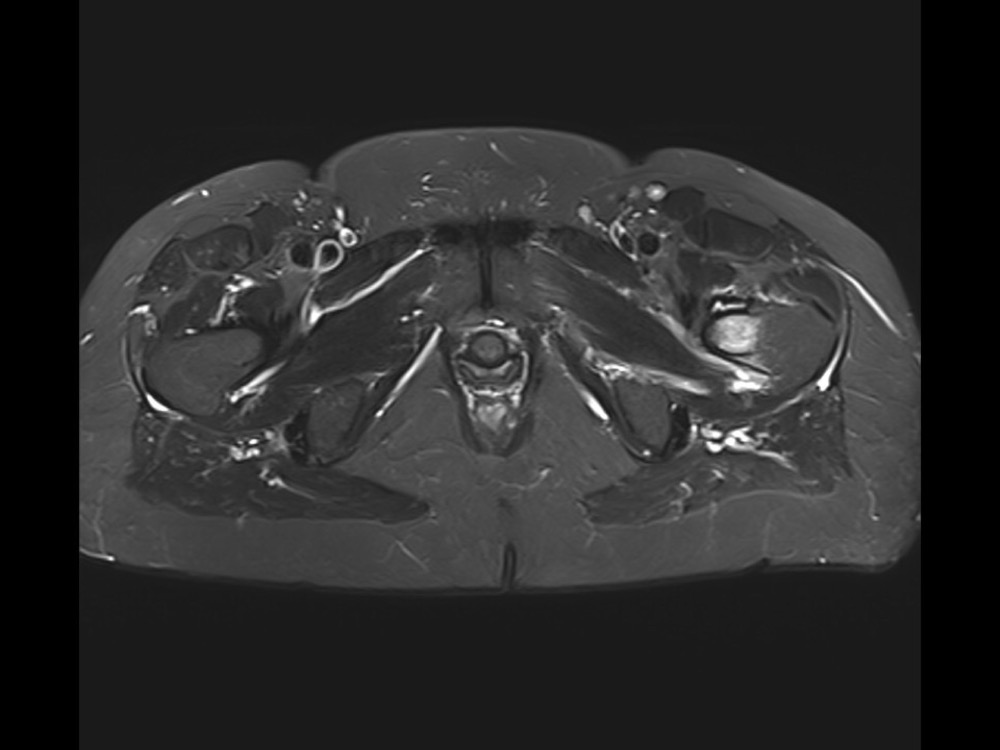

Douleurs de hanche

Linda Ouerd 06/11/2019